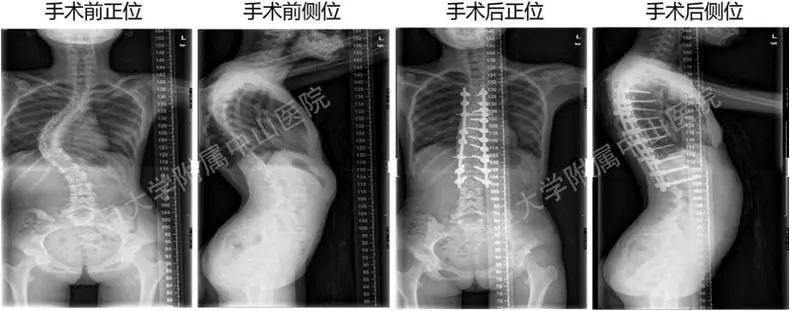

图五 脊柱侧弯的手术治疗

(图片来自复旦大学附属中山医院)

3、手术矫正治疗:仅适用于小部分角度较大(cobb角40°以上)、或者是角度加重较快、保守治疗无效的患者。但是针对先天性脊柱畸形、神经肌肉源性的脊柱畸形,这些患者可能需要脊柱外科医生尽早手术干预,以免出现侧弯相关的心肺功能障碍。前述病例中小李因严重脊柱侧弯(cobb角60°),为避免进行性加重(造成畸形、呼吸或心脏问题),予以手术干预(见图五:小李术前及术后脊柱侧弯矫正情况)。